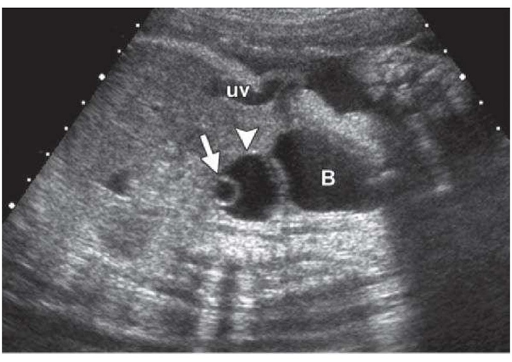

Siêu âm thấy nang trống âm buồng trứng là bị làm sao

Khi siêu âm thấy nang trống âm buồng trứng nhiều chị em không khỏi lo lắng vì không biết tính chất nguy hiểm của bệnh như thế nào. Trong phạm vi bài viết dưới đây chúng tôi xin chia sẻ những vấn đề cơ bản nhất để bạn đọc hiểu hơn về hiện tượng này.